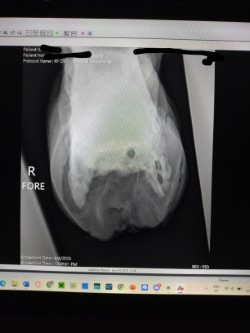

Rennie, a 2016 AQH, is a medical mystery; by all means, he shouldn't be standing, running, or jumping around the paddock. He was rescued in 2023 by a small family who help horses, skin and bones with a severe and constant limp in his right foreleg. We got him in February 2024, a great weight, but he still had a mysterious lameness that we couldn't figure out. After research, I found scoot boots. They took him from constant 3-4/5 lameness to a 1-2 lameness. Sound to be ridden (although he is just a paddock pet) We took x-ray at Texas A&M, the whole team was shocked, wondering how he is still alive with full fusion of his coffin, navicular and P3. His not only walking, but he is sound, happy, and a loving liberty pony. He came from a background of severe abuse. He has the physical and emotional scars of control-based training methods that left deep trauma: rope burns, whip marks, slashed legs, and twisted ears told a story of cruelty I wouldn’t wish on any animal. He had spent his final months before rescue in the auction pipeline.

I turned back to Rennie’s old farrier, the only one he and I trusted, but his flare-ups worsened, and without clear x-rays, we had little understanding of what was truly happening inside his hoof. I consulted my vet about quality of life, corrective shoeing, and every option we had left. When Texas A&M provided new x-rays, the truth was undeniable. His fusion was so severe that most professionals believed there was no choice but euthanasia. One corrective shoer refused to even see him, stating simply, "The horse should be put down."

But the team at Texas A&M saw what I saw—Rennie was defying the odds. Corrective shoeing wasn’t the answer. Traditional shoes would only add more stress, but Scoot Boots gave him freedom. They allowed his hoof to move as naturally as possible, relieving pressure without restricting movement. The specialists were amazed—not just at his ability to move, but at how much the boots had helped him. Without them, he wouldn’t be sound. Without them, I would have had to make the hardest decision.